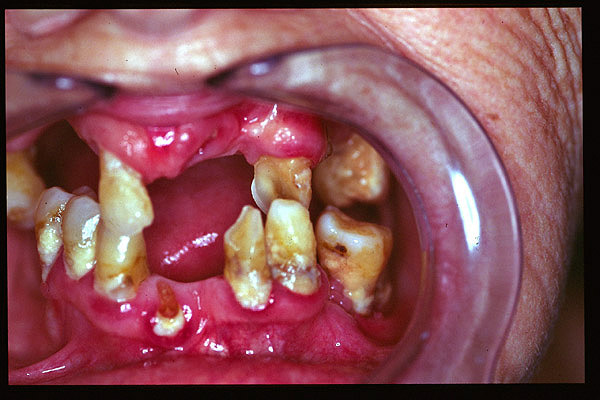

CM Caries y enfermedad periodontal avanzada